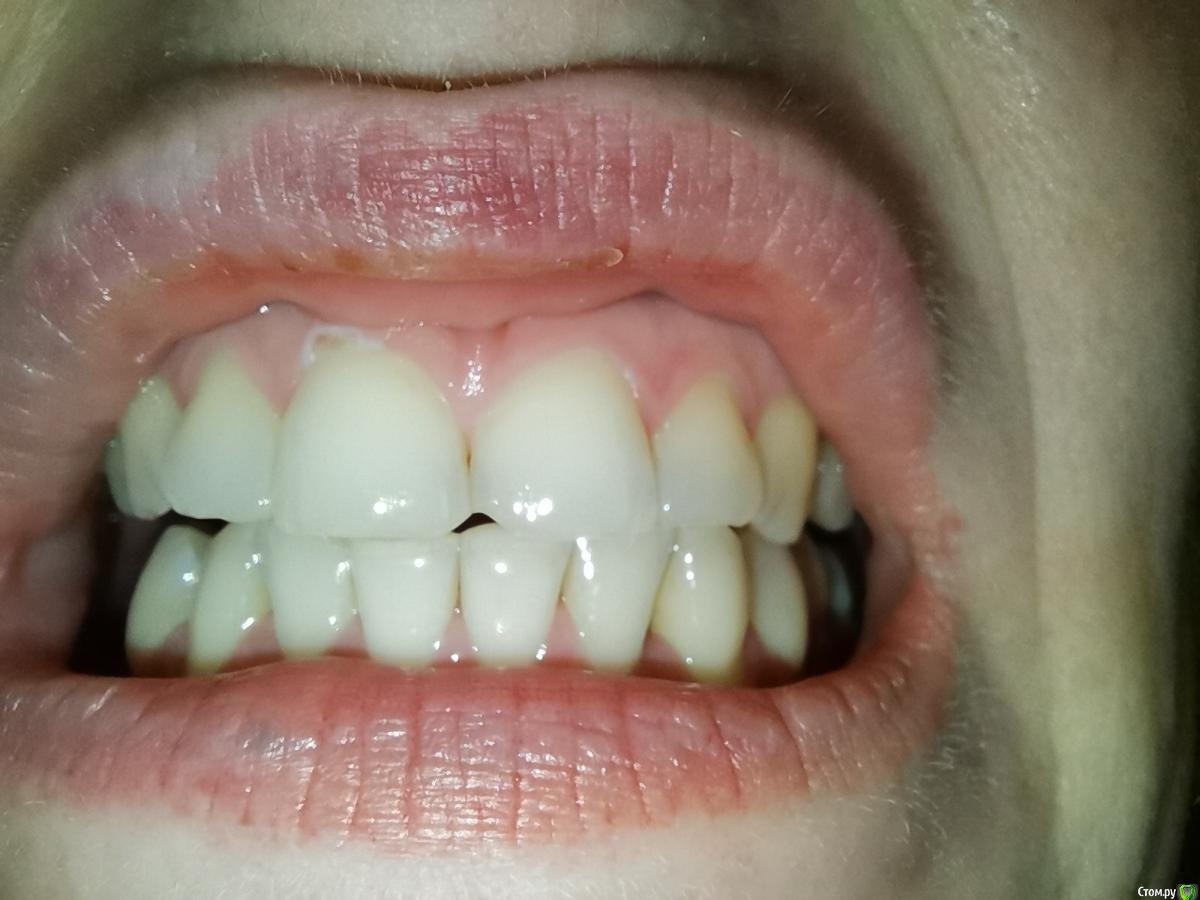

Прошу совета по поводу своих проблем с деснами. Они у меня не кровоточат, не болят, но между жевательными зубами у меня исчезли десневые сосочки и если зубы пошатать, то они как бы двигаются (если шатать от неба к губам то не шатается, если между зубами, то как бы отходят друг от друга и слышится треск неприятный). Также стали исчезать сосочки между центральным и верхним зубами и двойками - появились небольшие дырочки

Сделала к-т для следующего врача и сделала фото с к-т. Можете посмотреть, тяжёлый ли пародонтит во всей челюсти и особенно около левых верхних зубов с 4 по 7. Как лечиться и куда бежать?

У меня между нижним зубами с 4 по 4 и верхним между 1 и 2 начали появляться щели, межзубный сосчек исчезает какими то очень быстрыми темпами - 2 месяца назад все было хорошо. Может подскажите с чем это может быть связано? Может быть с нижним 8, которые удаляла как раз в октябре это как то может быть связано. Боюсь эти сосчки исчезнут навсегда (